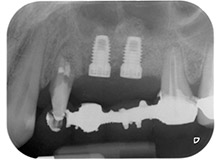

Enfin, après incision du périoste, le site a été suturé avec repositionnement passif d'un lambeau d'avancement coronaire, à l'aide d'un matériau de suture résorbable 5-0 (Fig. 15). La radio postopératoire montre les deux implants dans leur position verticale correcte (Fig. 16).

Résultat intermédiaire à deux mois

Les figures 17 et 18 présentent le résultat clinique deux mois après l'intervention chirurgicale. La dent 24 présentait une mobilité réduite, de classe I (Miller) et les tissus mous ne présentaient aucune inflammation. Pour prévenir toute nouvelle infection et pour éviter d'endommager l'attache épithéliale, aucun test n'a été pratiqué à ce stade. Une visite de contrôle a été programmée pour la prochaine incision et la mise en place des parties secondaires de cicatrisation, six mois après l'insertion des implants.